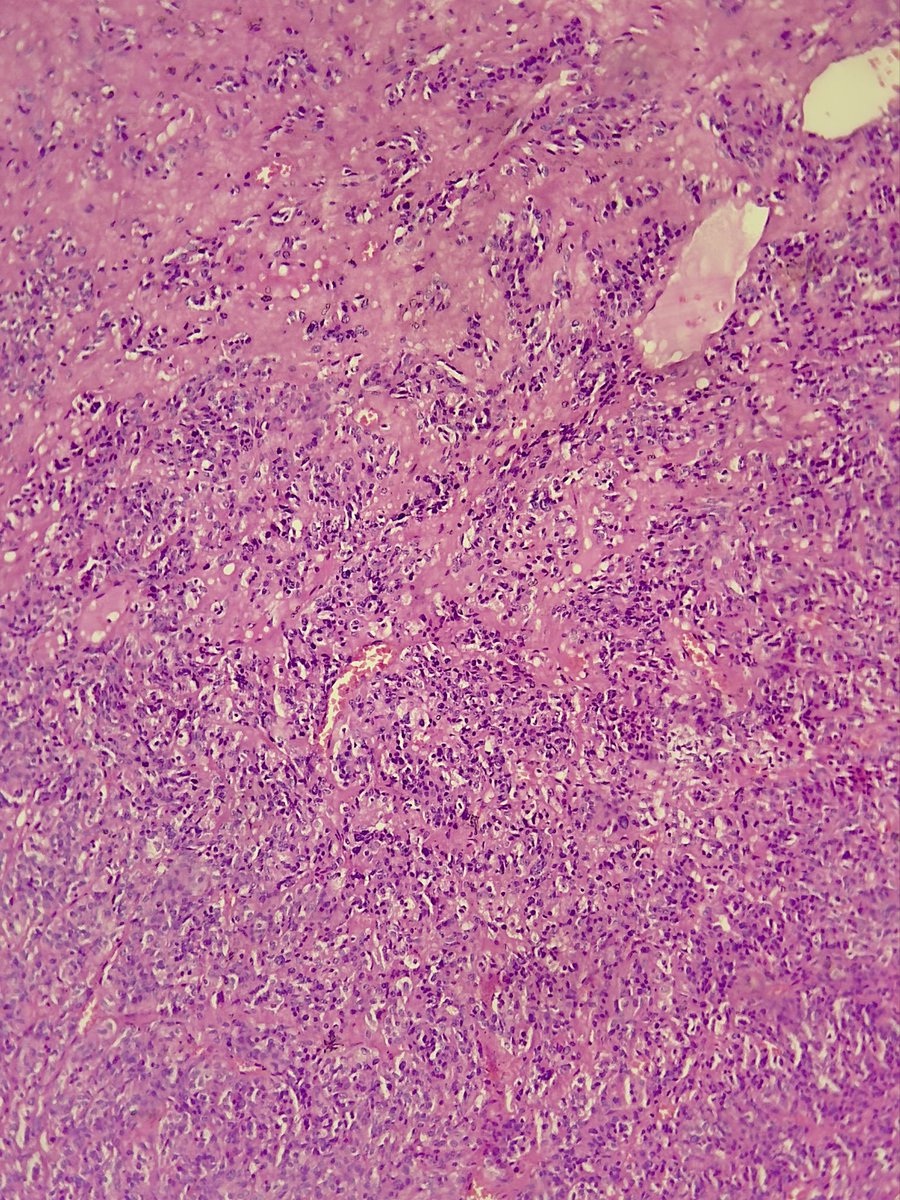

Kindly share your thoughts on this: Late 30s, About 4 years of recurring headache and worsening vision bilaterally. 👨🏾‍⚕️🔪-Well encapsulated huge suprasellar mass ?Pituitary macroadenoma No access to IHCs. #CNSPath #Neuropath #Endopath #Pathology

DrGeeONE's tweet image. Kindly share your thoughts on this:

Late 30s, About 4 years of recurring headache and worsening vision bilaterally.

👨🏾‍⚕️🔪-Well encapsulated huge suprasellar mass ?Pituitary macroadenoma

No access to IHCs.

#CNSPath #Neuropath #Endopath

#Pathology